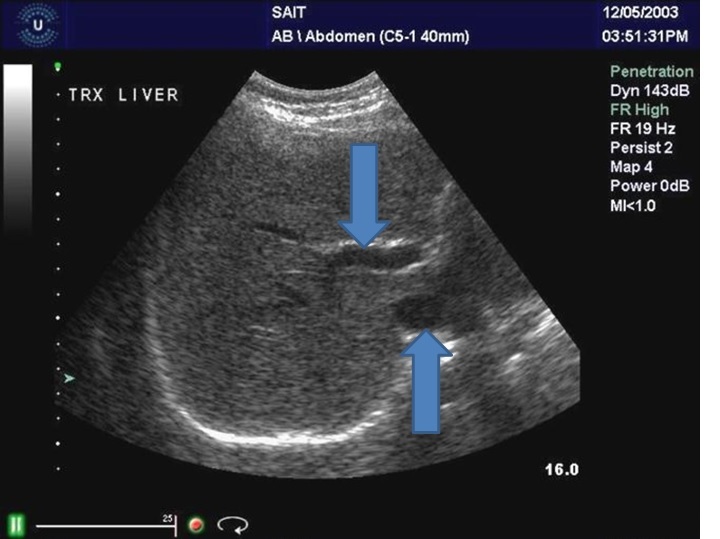

What is the structure?

Left portal vein